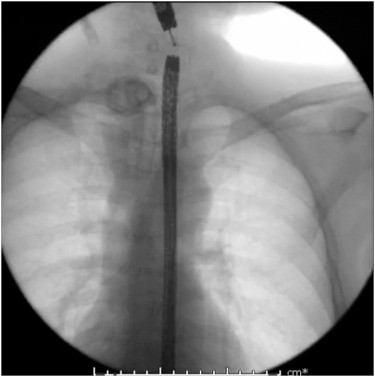

Fluoroscopy showing 2 endoscopes with tunnel creation.